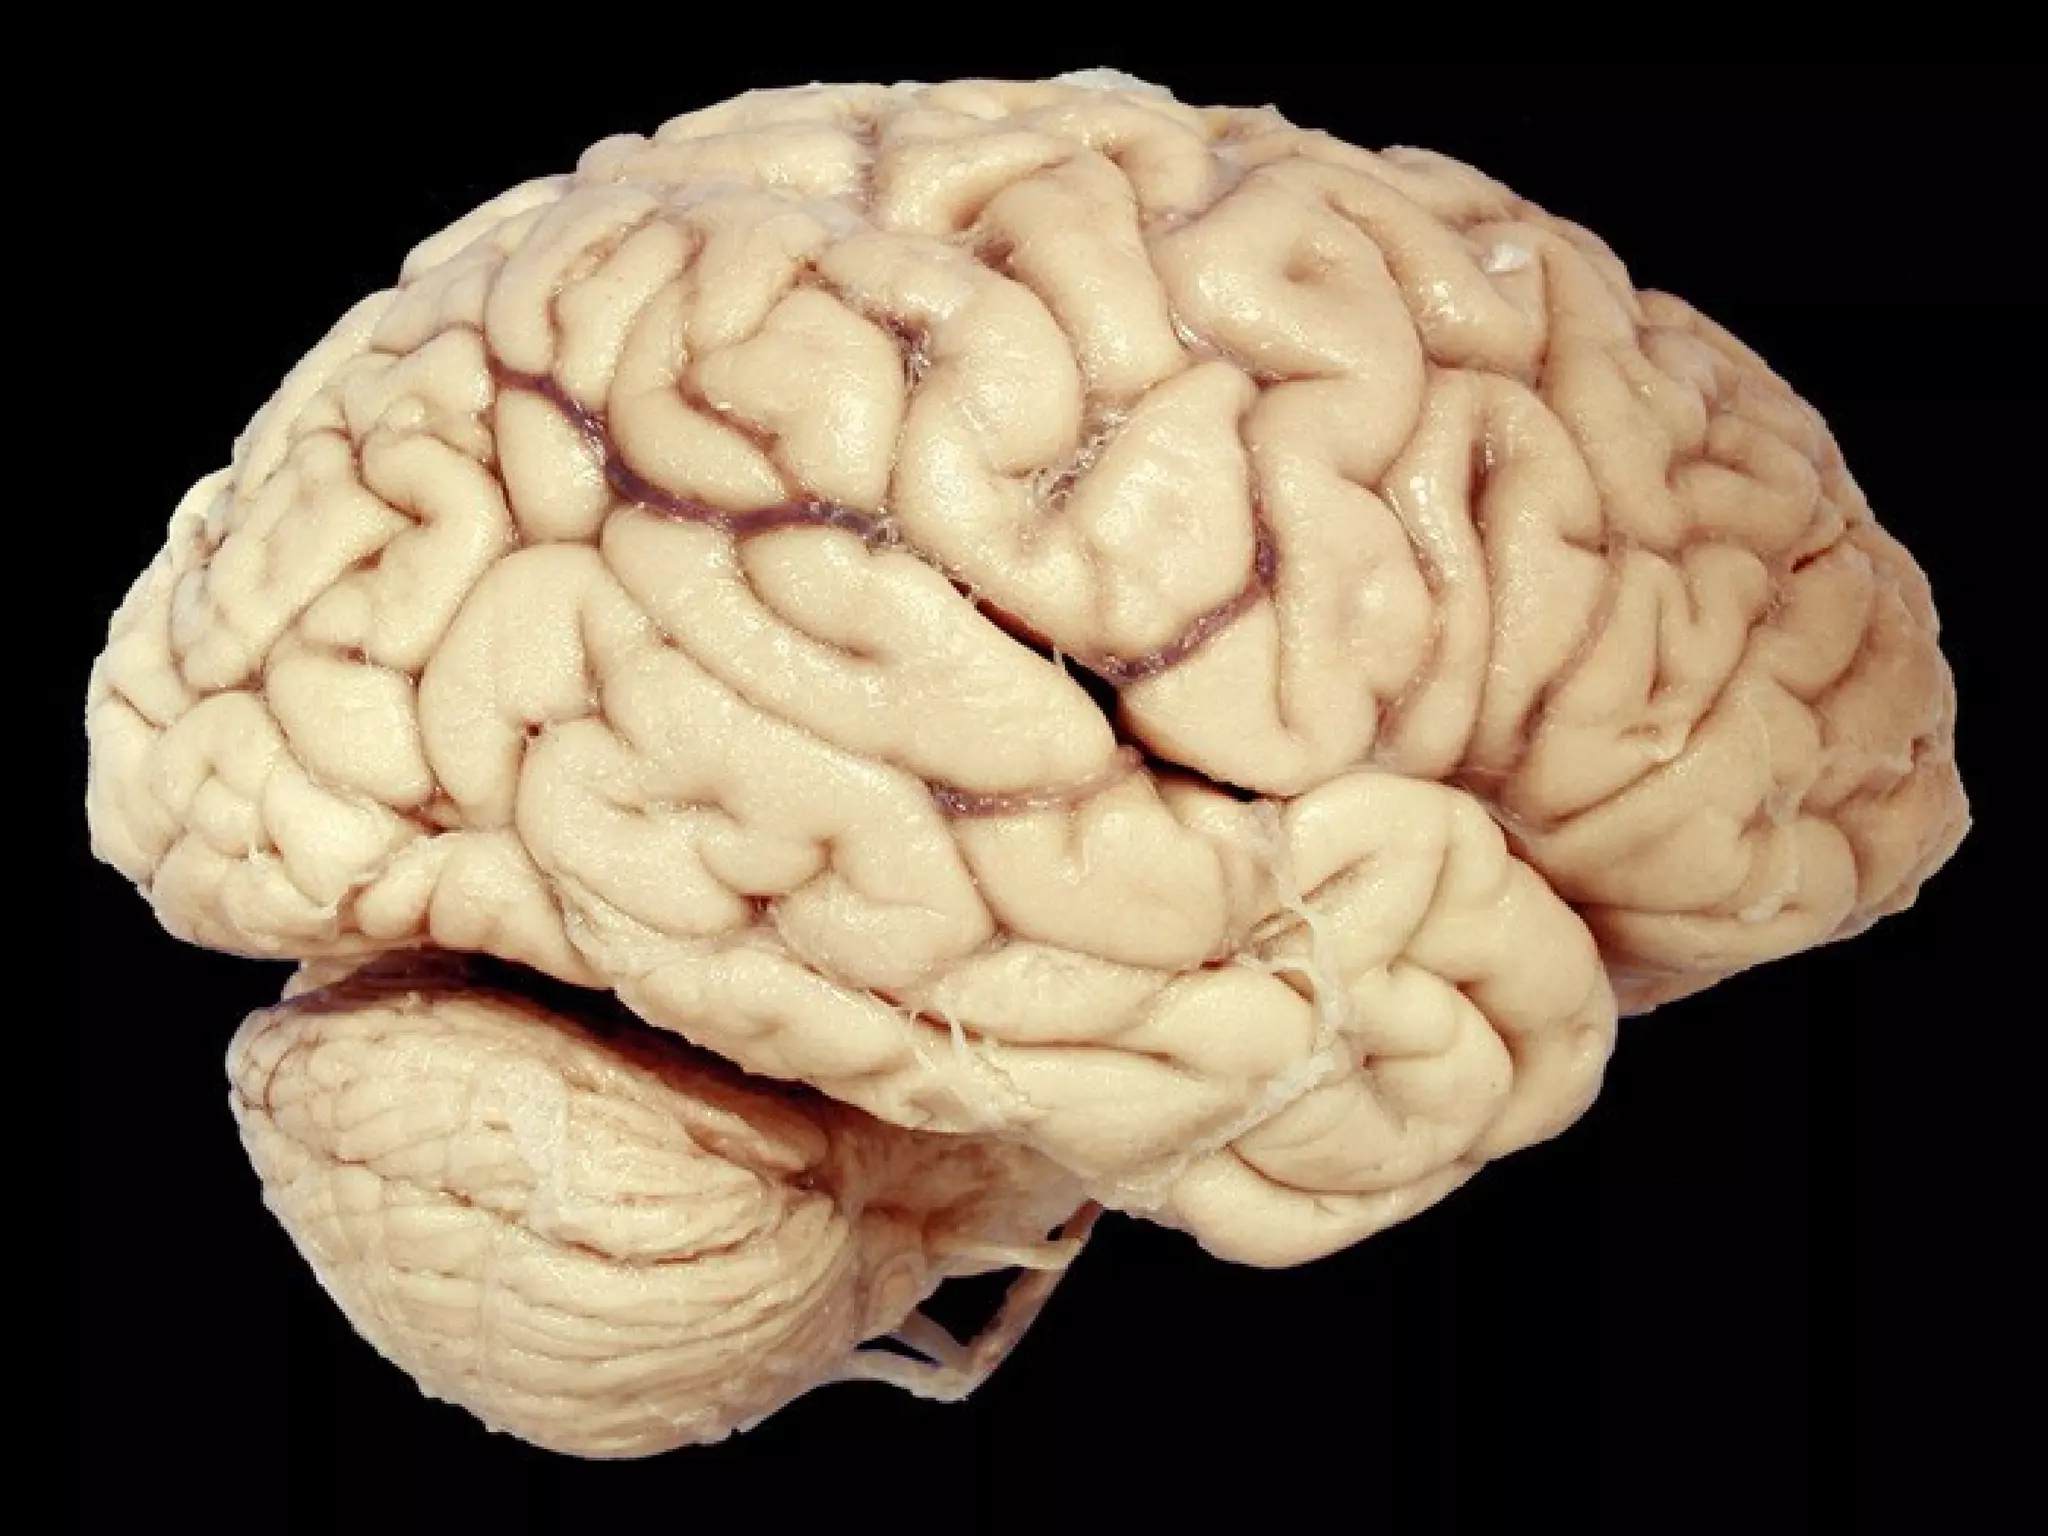

• #21 Flattened gyri often signify edema. Why? Ans: compression against the calvarium

• #114 Normal sulci.

• #115 Prominent sulci in cortical atrophy. Why are the sulci, NOT the gyri, prominent in atrophy? Ans: cortical LOSS